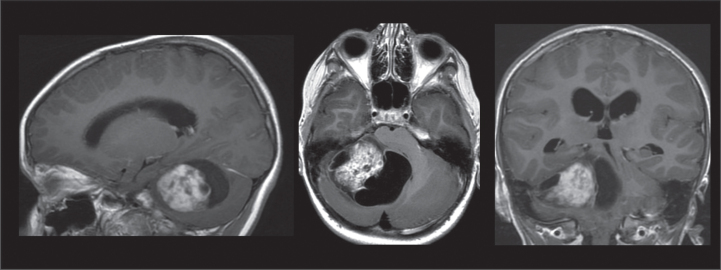

Abstract Image